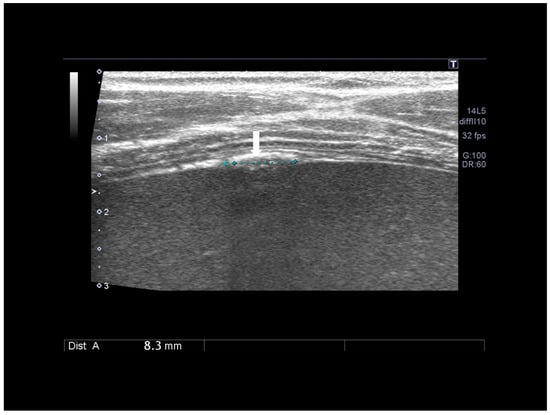

3.6. Thoracic Endometriosis

Thoracic endometriosis (TE) is an endometriotic lesion that involves the diaphragm, pleura, and/or lung. Lung is rare, but diaphragm lesions are not so rare [5,7,32]. The typical manifestation of diaphragmatic endometriosis is catamenial pneumothorax. Usually the diagnosis is performed using MRI in the absence of reports regarding ultrasound findings. Diaphragmatic endometriosis is characterized by ultrasound as small hypoechoic lesion (Figure 20 and Figure 21).

Figure 20. Diaphragmatic small nodule of endometriosis (see white arrow) confirmed at surgery.

Figure 21. Diaphragmatic endometriosis (see white arrow) confirmed at surgery (A,B).